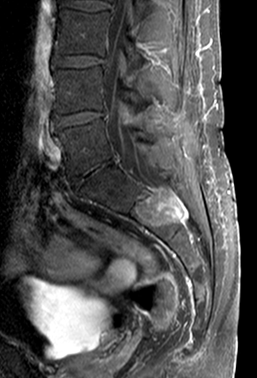

Ependymomas rather occur in adulthood (they can also be the metastases of primary cerebral ependymomas) thoracic spinal chord, medullary cone, filum terminale.

MRI: On T1 withed images it shows isointense with the spinal chord, while on T2W images it is hyperintense.

Contrast enhancement is strong, it can be inhomogeneous.